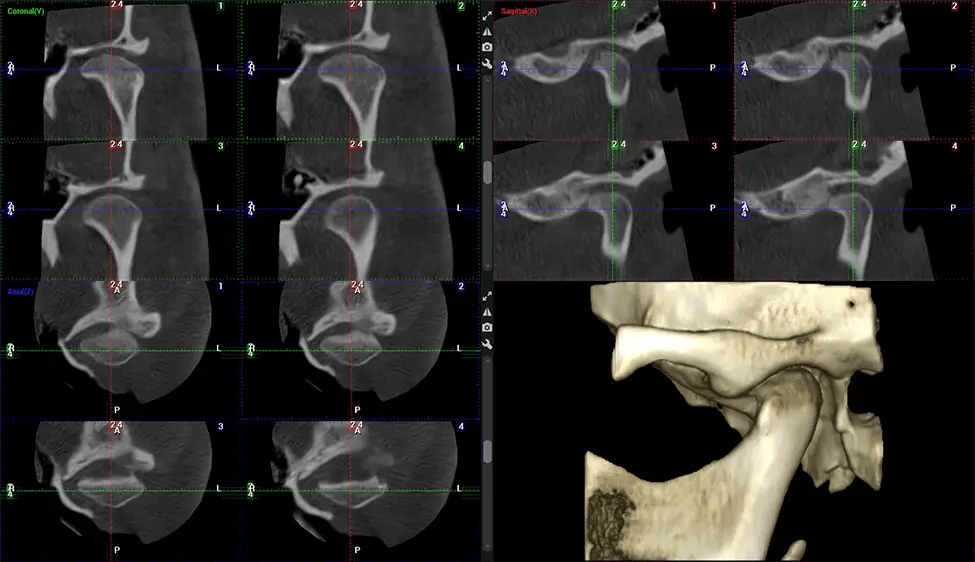

Cone Beam Computed Tomography (CBCT) is an advanced imaging technique used in dentistry and maxillofacial surgery to obtain detailed 3D images of the oral and maxillofacial structures. At Dr G Dental Studio, our CBCT scanners utilize a cone-shaped X-ray beam and a specialized detector to capture images from different angles. A computer then combines these images to create a 3D representation of the patient’s oral anatomy.

This 3D scan, called cone beam computed tomography, gives your dentist a more complete image of your oral anatomy and disease processes than a traditional X-ray. Unlike conventional X-rays, which capture a 2D image of your mouth from various angles, a 3D scan takes multiple digital X-rays for one image. It provides a complete view of your jaw, teeth, nerves, and soft tissues. This enhanced view allows dentists to detect minor issues not visible in traditional 2D scans, such as impacted wisdom teeth or bone fractures in the sinus cavity.

The patient is first positioned in the CBCT scanner, which typically consists of a rotating arm that houses the X-ray source and a detector. The patient’s head is immobilized to ensure accurate image capture. The X-ray source and detector rotate around the patient’s head, capturing various X-ray images from multiple angles. As the X-ray source rotates, it emits the cone-shaped X-ray beam towards the detector. The detector captures the X-ray images, which are then processed by the CBCT software.

After the scanning process, the captured X-ray images are processed by the CBCT software, which applies algorithms to reconstruct a detailed 3D image of the scanned area. The software compiles these individual X-ray images and creates a digital 3D representation of the patient’s anatomy. The reconstructed 3D CBCT image can be viewed and analyzed by the dentist or radiologist. This image can be manipulated, rotated, and zoomed in or out to examine specific structures and evaluate the patient’s condition.

Planmeca Viso G7 CBCT ( Cone Beam CT Scan ) is designed to surpass the demands of industry leaders, specialists, and large institutions. It’s has a large ø25×30 cm sensor with four built-in cameras. It can capture unlimited volume sizes from a ø3×3 cm to a ø30x30cm volume capturing the skullcap through C7 on the cervical spine. The Planmeca Viso G7 offers the industry’s largest single volume scan of ø30×19 cm. It’s poised to handle advanced imaging modalities such as Planmeca ProFace® and Planmeca 4D™ Jaw Motion technology. The occipital head support allows an unimpeded view of facial tissue.